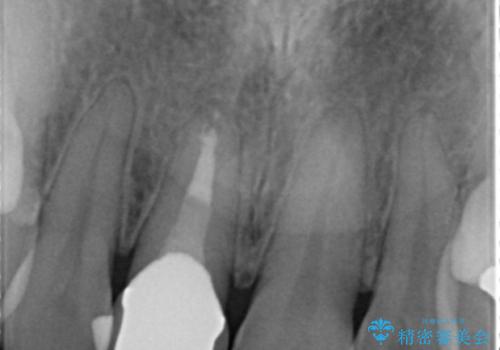

患者様の天然歯はグラデーションがあり切縁(歯冠の先端)はやや透けていて透明感があるのに対し、前歯(右上1)の差し歯はやや黄色く不透明で単調な色味でした。

患者様のご希望により、右上1はジルコニアクラウン(スペシャル)、右上5はジルコニアクラウン(スタンダード)へやりかえることにしました。

再根管治療に関しては、患者様がご希望されず症状もないため行っておりません。

ご予算の都合とご希望により、右上5の土台はやりかえずに元の土台のまま治療を進めました。